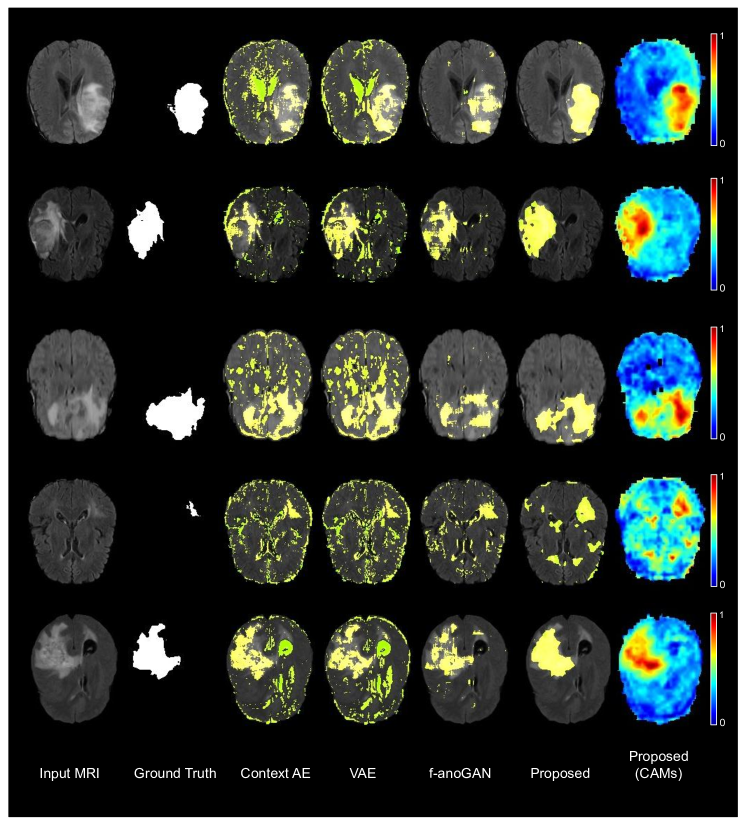

Qualitative evaluation.

Visual results of the proposed and existing methods are depicted in Figure 2. We can observe that our approach identifies as anomalous more complete regions of the lesions, whereas existing methods are prone to produce a significant amount of false positives (top and bottom rows) and fail to discover many abnormal pixels (top row).

Refer to caption

Figure 2: Qualitative evaluation of the proposed and existing high-performing methods.